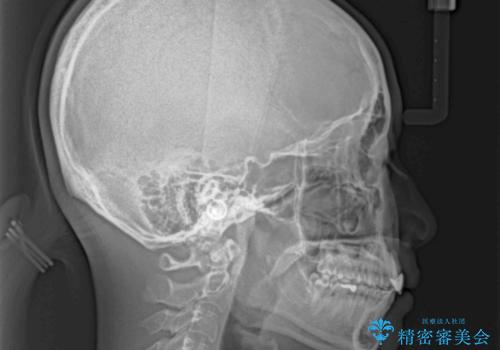

長時間のマウスピース装着と、患者様自身でのゴムかけに協力いただき、口元の突出感をしっかりと改善することができました。

前歯のオールセラミッククラウンもまるで本物の歯のように仕上がり、患者様には大変満足していただきました。